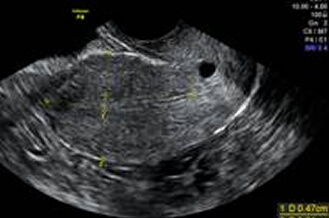

Conception may be affected by many factors, such as uterine myomas, chocolate cysts, endometrial thickness, and the number of antral follicles. All of these can be gathered by vaginal ultrasound scans.

Uterine Myoma